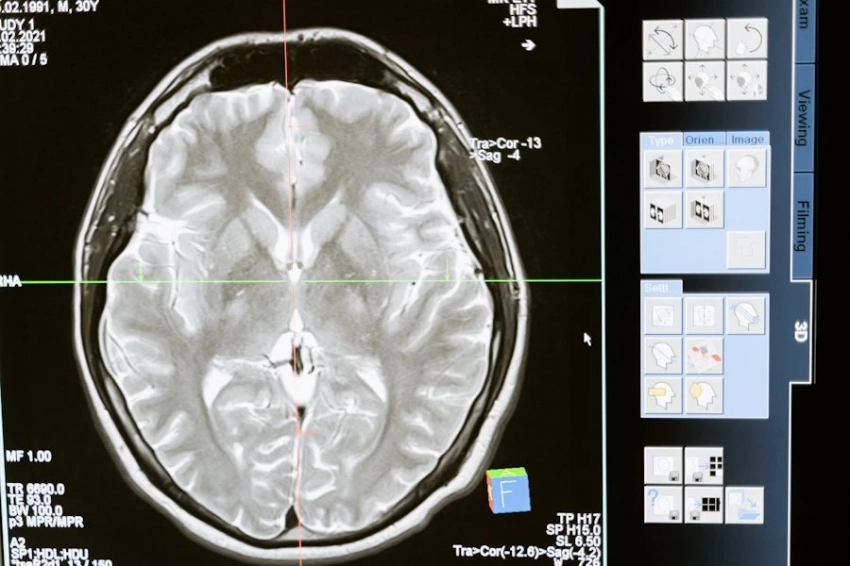

Учёные из Университета Шербрука, проведя исследования, пришли к выводу, что проблемы с когнитивными функциями, деменция и другие патологии мелких сосудов головного мозга чаще бывают у женщин с низким уровнем гормона эстрогена. Это означает, что здоровье сосудов мозга связано с длительностью воздействия гормонов. Проведенное исследование основывалось на материале, который был предоставлен 9 тысячами добровольных участниц в постменопаузе. Связь между двумя факторами не означает, подчёркивают учёные, что низкое воздействие эстрогена является причиной проблем с мелкими сосудами головного мозга. Микроангиопатии и мелкоочаговые болезни, возникающие в артериолах и капиллярах, вызывают нарушения нормального кровоснабжения и функционирования мозга.

Факторы, которые негативно воздействуют на состояние сосудов мозга и на когнитивные функции человека, давно известны. Это атеросклероз, гипертония, диабет, старение организма. Тем не менее, связь между продолжительной репродуктивной жизнью и низким риском заболеть деменцией, существует и она доказана исследованием биологов.